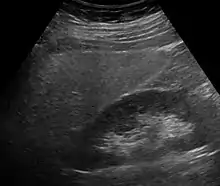

Imaging studies are often obtained during the evaluation process. Ultrasonography reveals a "bright" liver with increased echogenicity. Pocket-sized ultrasound devices might be used as point-of-care screening tools to diagnose liver steatosis. [30] [31] Medical imaging can aid in diagnosis of fatty liver; fatty livers have lower density than spleens on computed tomography (CT), and fat appears bright in T1-weighted magnetic resonance images (MRIs). Magnetic resonance elastography, a variant of magnetic resonance imaging, is investigated as a non-invasive method to diagnose fibrosis progression.[32] Histological diagnosis by liver biopsy is the most accurate measure of fibrosis and liver fat progression as of 2018.[8] Conventional imaging methods, such as ultrasound, CT and MRI, are not specific enough to detect fatty liver disease unless fat occupies at least 30% of the liver volume.[33]